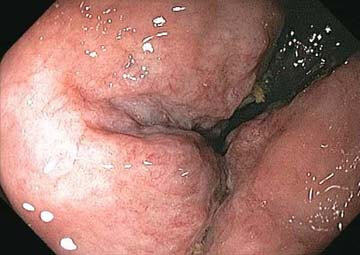

Hình ảnh trĩ nội

Triệu chứng bệnh trĩ nội độ 3: Cảm giác đau khi đi đại tiện sẽ nghiêm trọng hơn, các búi trĩ nội gia tăng kích thước và sa ra ngoài hậu môn khi đi đại tiện, thậm chí khi ho mạnh, hắt hơi hoặc vận động mạnh mà không tự co lại được phải dùng tay đẩy vào. Hiện tượng chảy máu hầu như không còn xuất hiện.

Triệu chứng trĩ nội độ 4 (giai đoạn cuối): Các búi trĩ thường xuyên bị sa ra ngoài và dùng tay tác động cũng không co lại được (kể cả lúc không đi đại tiện).